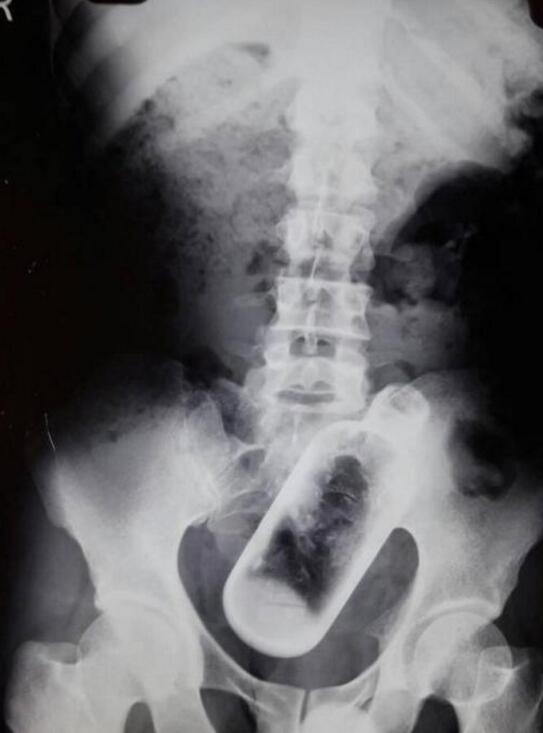

- 印度男子酒后胃疼去照X光 肚中现16厘米长酒瓶子

- 时间:2017-04-28 09:37:27